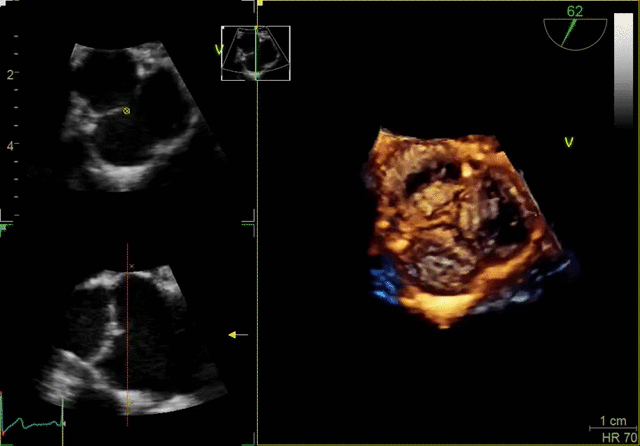

Ultra-high single-beat volume rates With TEE procedures growing, so is the need to find ways to achieve the benefits of 4D imaging without compromising productivity. VmaxTM enabled by cSound™ 2.0 offers ultra-high 4D volume rates acquired in single beat acquisition with no loss of image quality. Elimination of ECG gated multibeat/stitching acquisition provides enhanced overview of structures and function in cases with high and/or irregular heart rhythm - which potentially reduces interventional procedure time and improves patient outcomes.

4D TEE color imaging with Vmax

FlexiZoom

Triplane